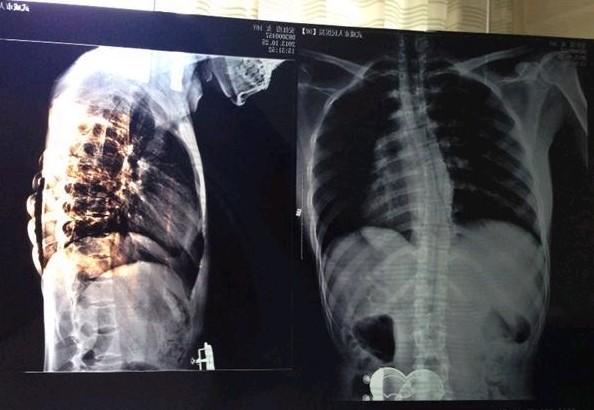

- 安红霞的X光片,可见脊柱呈S型,医生说如果不及时手术,姑娘很可能会瘫痪,甚至有生命危险